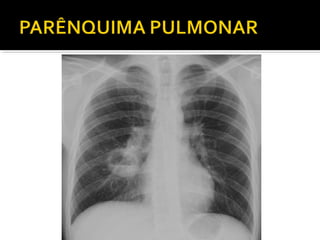

Este documento fornece parâmetros técnicos para realizar uma radiografia de tórax, incluindo posicionamento correto do paciente, dose adequada de radiação e estruturas anatômicas a serem avaliadas, como coração, pulmões, pleura, diafragma e ossos do tórax.